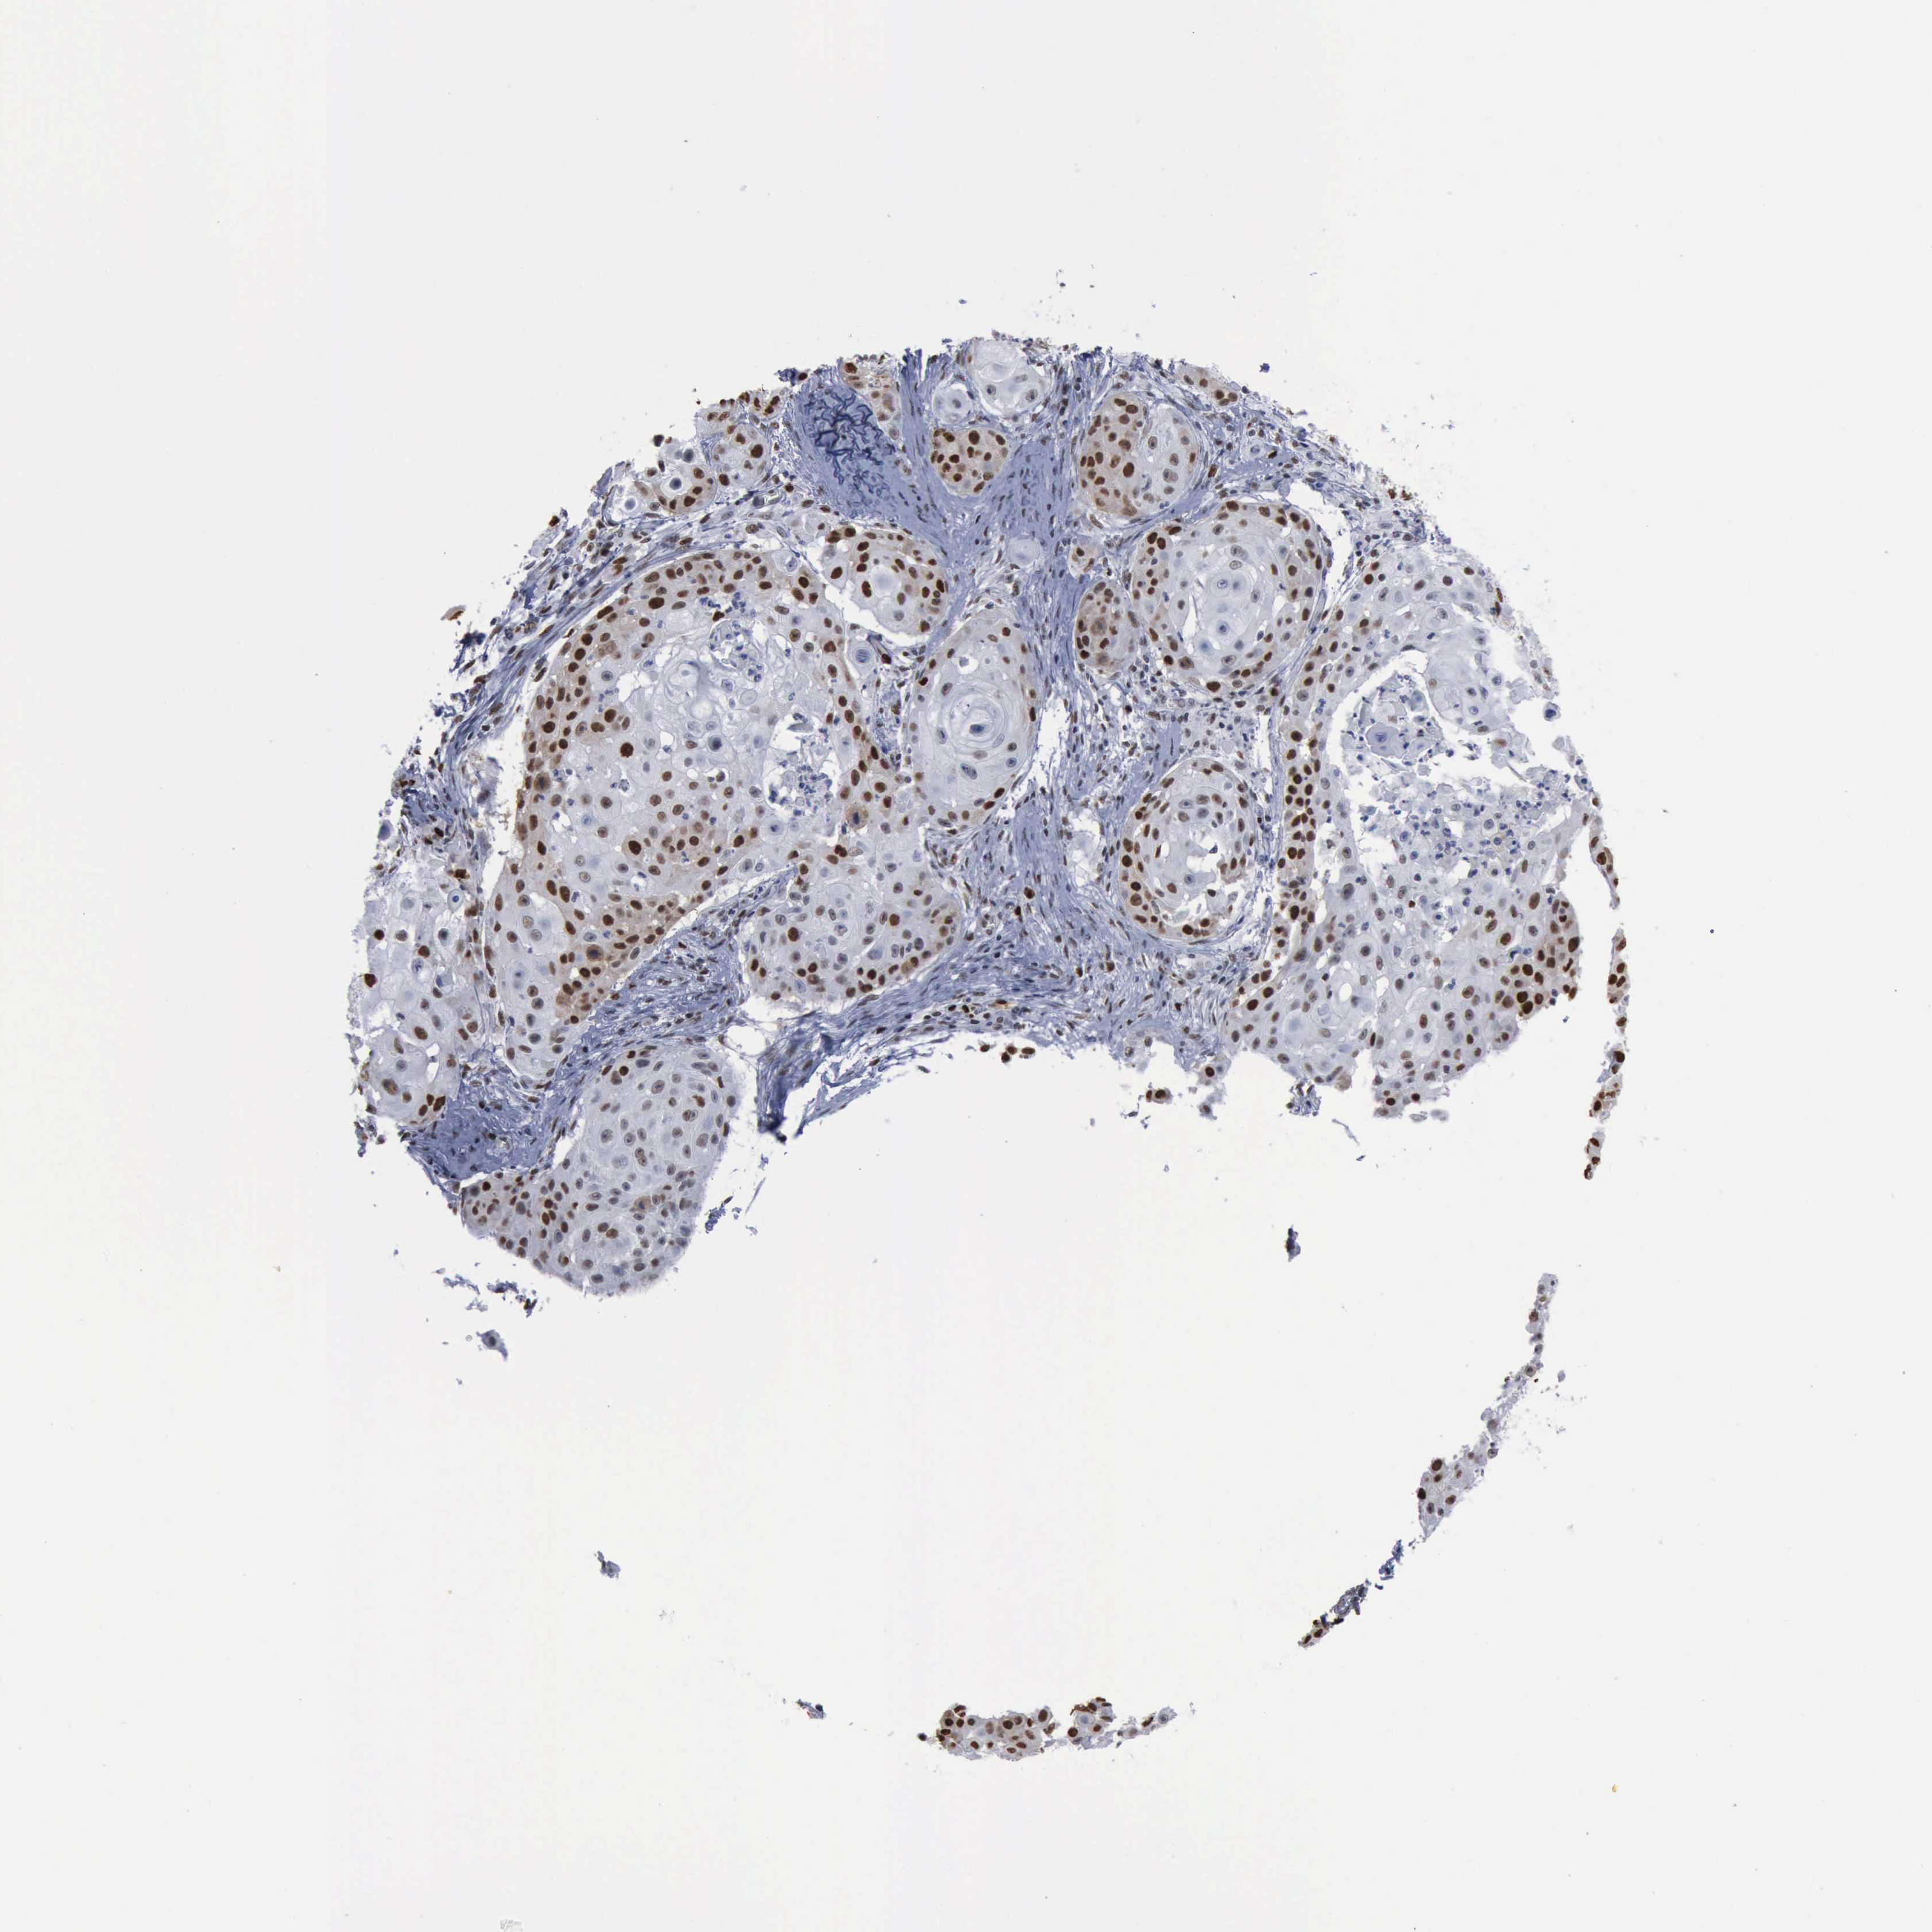

SKIN CANCER - Protein expressioni

A mouse-over function shows sample information and annotation data. Click on an image to view it in a full screen mode. Samples can be filtered based on level of antibody staining by selecting one or several of the following categories: high, medium, low and not detected. The assay and annotation is described here.

Each image is clickable and will lead to virtual microscopy that enables deeper exploration of all samples and also displays staining intensity scores, fraction scores and subcellular localization as well as patient and tissue information for each sample.

HPA030521

HPA030522

HPA030523

CAB000148

CAB080240

CAB080241

CAB080242

Staining

High

Medium

Low

Not detected

Intensity

Strong

Moderate

Weak

Negative

Quantity

>75%

75%-25%

<25%

None

Location

Nuclear

Cytoplasmic/membranous

Cytoplasmic/membranous,nuclear

Basal cell carcinoma

Squamous cell carcinoma, NOS

Squamous cell carcinoma, metastatic, NOS